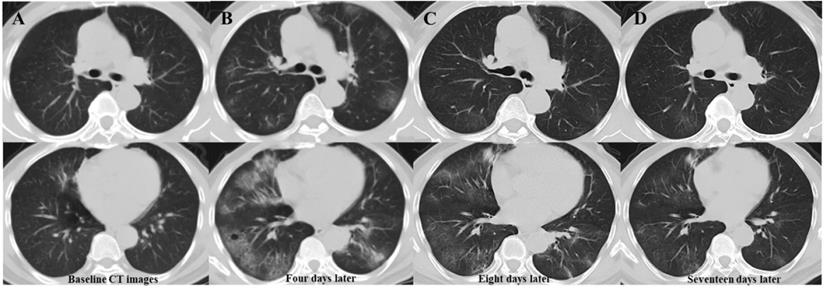

Table 3 presents follow-up CT characteristics of patients with COVID-19. During treatment, primary lesion progression was significantly more common in patients with new lesions than in those without. (90.5% vs. 14.3%, P=0.000). Most patients (37/42, 88.1%) developed new lesions when the primary lesions progressed. After their occurrence, most of the newly developed lesions (32, 76.2%) were directly absorbed (Figure 2). On the latest CT, patients with new lesions had more complex residues than those without new lesions.

Serial chest CT images of a 63-year-old man with confirmed COVID-19 pneumonia. Baseline CT images (column A) show patchy ground-glass opacity (GGO) in the right middle lobe. Four days later (column B), the primary lesion progress, and multiple new GGOs occur in previously involved and uninvolved lobes. Follow-up CT images (column C) eight days after admission show absorption of the primary and newly developed lesions. The latest follow-up CT images (column D) 17 days after admission show significant absorption of lesions, with little residue. Abbreviations: COVID-19: coronavirus disease 2019; GGOs: ground-glass opacities.